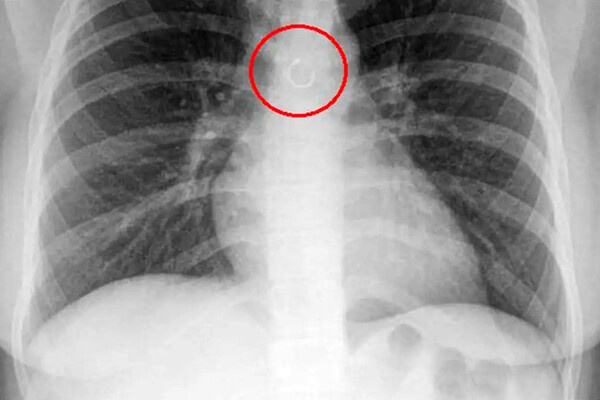

Женщина обнаружила, что потерянное кольцо в носу попало в ее легкие

Во время обследования выяснилось, что украшение из пирсинга в носу каким-то образом оказалось глубоко в дыхательных путях девушки и застряло в легких. Металлический элемент находился всего в полумиллиметре от аорты, что могло привести к опасным последствиям, добавили медики.